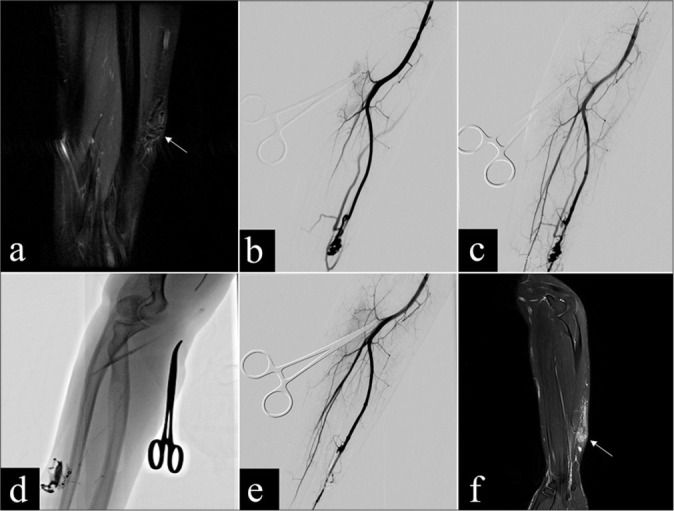

Objectives: Congenital arteriovenous malformations (AVMs) are characterized by abnormal connections between arteries and veins, often presenting challenges in treatment due to their complex vascular structure. Endovascular therapies, including embolization techniques, have become integral in managing AVMs, yet optimal treatment strategies remain under investigation. This retrospective study aimed to evaluate the safety and efficacy of percutaneous glue embolization of n-butyl cyanoacrylate (nBCA) combined with arterial embolization in treating extracranial AVMs.

Material and methods: This retrospective study included 11 patients with extracranial AVMs who underwent percutaneous injection of nBCA glue embolization combined with arterial embolization at our institution between May 2015 and October 2023. Angiographic classification was performed using the Cho-Do vascular imaging system and the Schobinger classification system to categorize the AVMs. Treatment efficacy was assessed based on the percentage of vessel occlusion observed in angiography or imaging studies. The occurrence of major and minor complications was also evaluated.

Results: Eleven patients received 16 treatments, involving a combination of arterial and percutaneous embolization techniques. Five cases achieved complete recovery, while four cases showed significant improvement, resulting in an overall treatment success rate of 81.8%. Favorable outcomes were observed in terms of symptom alleviation and lesion occlusion. Adverse events were minimal, with transient pain and edema being the most common postoperative complaints. Only one case of mild post-operative complication occurred.

Conclusion: Percutaneous glue embolization combined with arterial embolization proves to be a safe and effective treatment modality for extracranial AVMs, with acceptable rates of complications and favorable treatment outcomes.